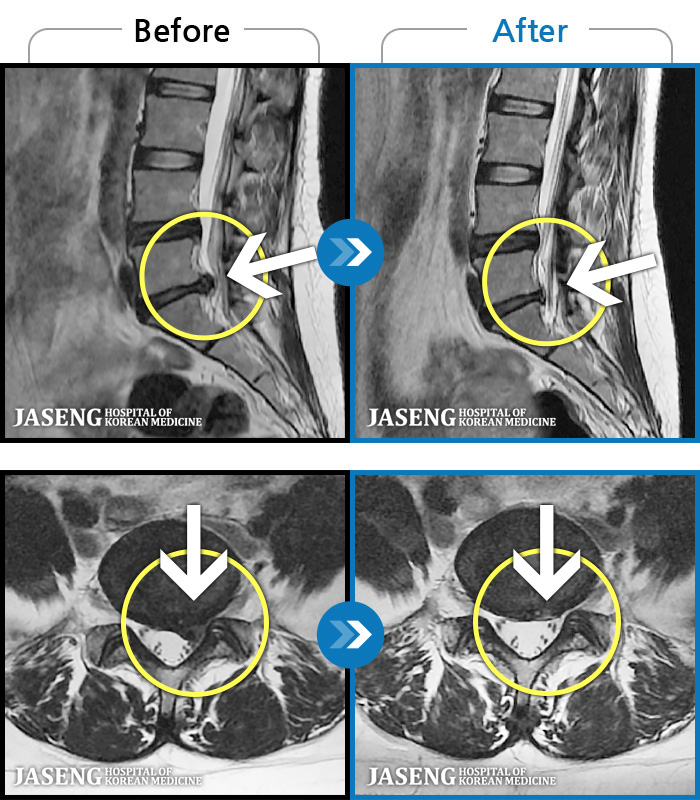

2-3년간 디스크로 허리통증과 하지방사통으로 여러 치료하였으나 나아지지 않는 증상